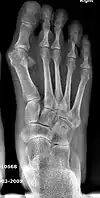

- For severe bunion deformity correction (Fig. 7)